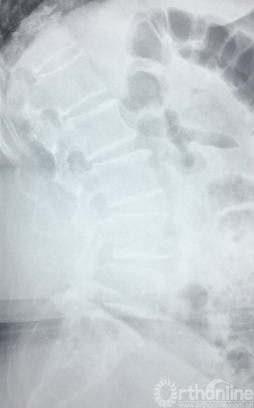

过伸位X片